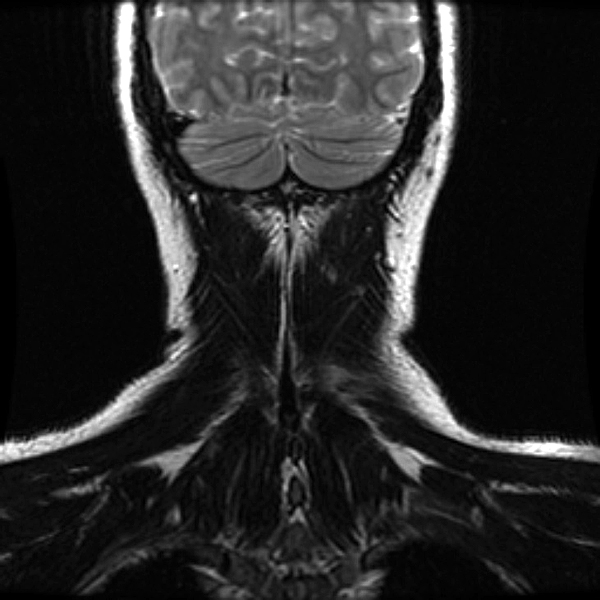

once i got back home and checked out my scans in osirix (the mac os x application to view DICOM medical imaging slides), i was blown away. talk about invasive: you haven't seen intimate until you've looked at photos of the inside of your body. the coolest part is since the scans were done in cross-sections, i can animate the scans so it looks like the beam is passing through my neck and head (all 800+ images). i've always known that inside my body was all sorts of muscles and veins and organs, but i guess i was hoping for something less messy, maybe circuit boards and memory chips instead. i know MRI's were first used in the late 60's, but this is my first time experiencing the technology in-person and it's pretty amazing. talk about futuristic! to be able to see with so much detail the insides of my body without having to cut me open! if scientists can do this, what else can they do? my only regret is they only imaged me from my shoulder up. i'd love to have a full-body scan. maybe i can fake some sort of internal injury and get my doctor to okay the procedure. i recommend anyone who's never had an MRI done to do so when they have the chance.